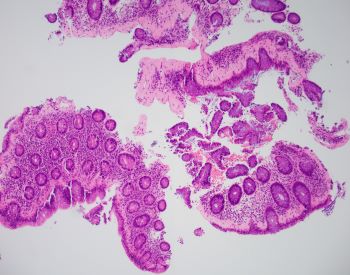

A 43-year-old female presents with chronic unexplained diarrhea. Colonoscopy shows normal mucosa. A random colon biopsy is taken (shown below).

The most likely diagnosis is collagenous colitis. Clinical presentation typically consists of chronic unexplained diarrhea with or without abdominal pain, nausea, vomiting, and weight loss. A colonoscopy shows normal colonic mucosa or mild nonspecific changes. Collagenous colitis is a type of microscopic colitis. Histologic sections show a thickened subepithelial collagen band (>10 μm) with inflammatory cell entrapment and capillary proliferation. A trichrome special stain can highlight the collagen deposition. The surface epithelium may show reactive changes or a mild increase in intraepithelial lymphocytes. The other type of microscopic colitis is lymphocytic colitis, and would show more prominent intraepithelial lymphocytes than collagen deposition. The differential diagnosis may include amyloid deposition. Amyloidosis sometimes shows subepitheilal deposition, however most often involves blood vessels. A congo red special stain would highlight amyloid and inflammation would not be increased. Ischemic colitis shows diffuse lamina propria hyalinization and scleroderma involving the gastrointestinal tract shows fibrosis of the muscularis propria.